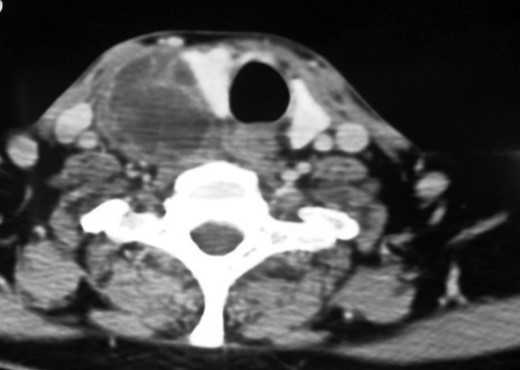

Computed tomography (CT) scan of the neck (with contrast) indicated a heterogeneously enhancing lesion with multiple cystic spaces along the postero-lateral aspect of the right lobe. The lesion was seen to push the adjacent lobe anteriorly to the left (Fig. 2). The lesion was also displacing the right common carotid and the internal jugular vein laterally; however, a well-defined fat plane was seen between the lesion and the carotid sheath. No such plane was seen between the lesion and the adjacent thyroid lobe (Fig. 3).

Contrast enhanced CT neck (coronal section). Coronal section showing good plane of delineation between the lesion and carotid sheath, along with mass effect on the thyroid gland and the right common carotid.